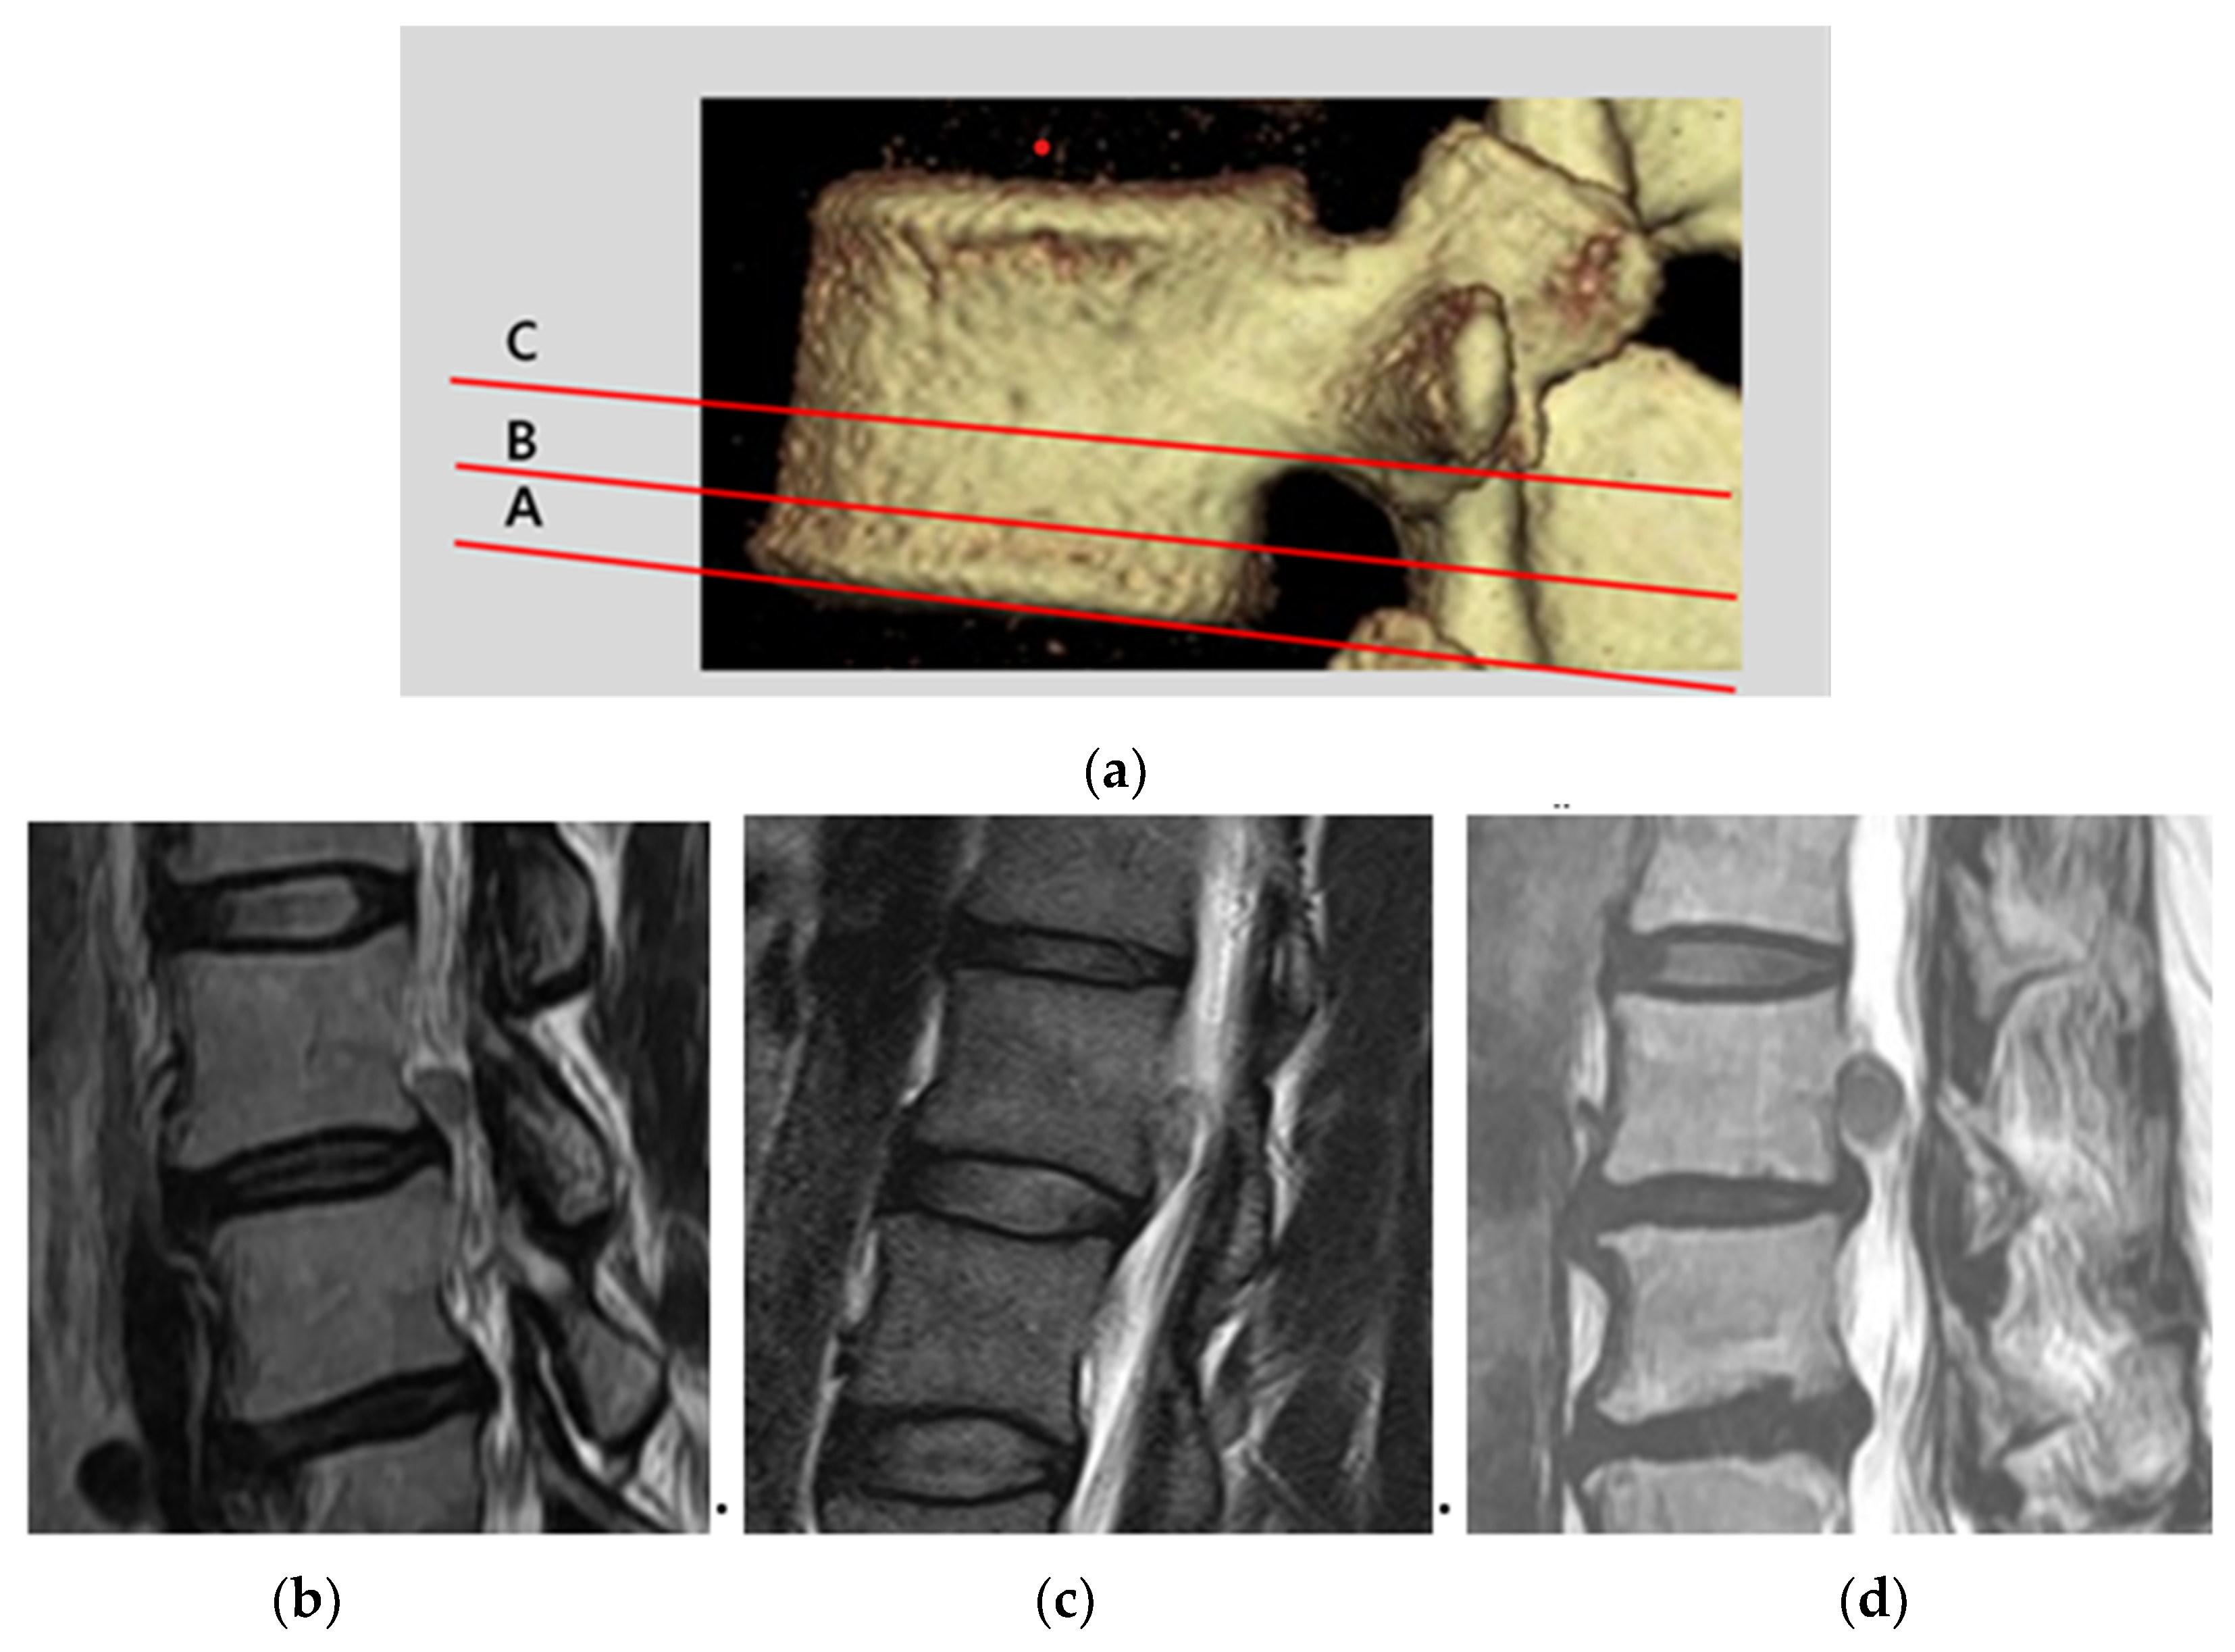

2.3. Classification of Upward Disc Migration and Analysis of Radiologic Parameters

Disc herniations, displaced away from the extrusion site, above the endplate level of the upper vertebral body were defined as upward migrated disc herniations [8]. We classified 3 types (A, B, and C) of migration zones (Figure 1a) using sagittal T2-weighted MRI. Type A represented herniations where the upward migration extent was less than half of the interval from the upper disc end plate line to the inferior pedicle margin (Figure 1b). Type B represented herniations where the upward migration extent was more than half of the interval from the upper disc end plate line to the inferior pedicle margin (Figure 1c). Type C represented herniations where the upward migration extent was more than the lower margin of the pedicle (Figure 1d, highly migrated disc herniation) [5,9].

Figure 1. Classification of upward ruptured disc migration. (a) Type A, upward migration extent was less than half of the interval from the upper disc end plate line to the inferior pedicle margin; (b) type B, upward migration extent was more than half of the interval from the upper disc end plate line to the inferior pedicle margin; and (c) type C, upward migration extent was more than the lower margin of the pedicle (d).